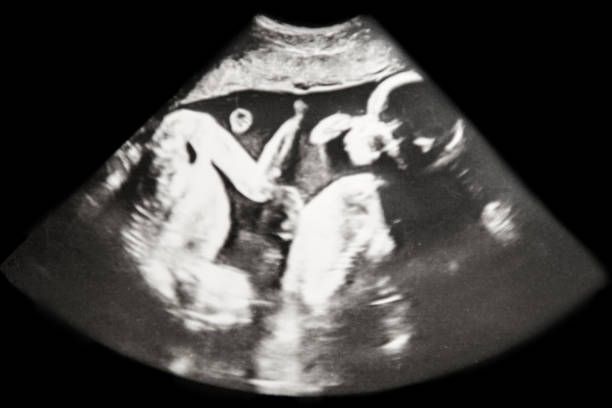

Las mujeres embarazadas de gemelos > 45 años tienen más riesgo de preeclampsia y cesárea

Cada vez tenemos más gestantes mayores de 45 años. Y dentro de este rango de edad también hay un número creciente de gestaciones  gemelares. Recientemente hemos publicado una trabajo estudiando las complicaciones de las gestaciones gemelares en mujeres mayores de 45 años frente a gestaciones únicas en mujeres de la misma edad.

Hemos concluido que las gestante de gemelos tenían más riesgo de preeclampsia y de terminar en cesárea frente a las gestaciones únicas. Son embargo el riesgo de diabetes gestacional fue similar en ambos grupos.

Baby Ultrasound of Identical Twins laying upside down (week 22)

La prematuridad también fue mayor en el grupo gemelar frente al de gestaciones únicas.